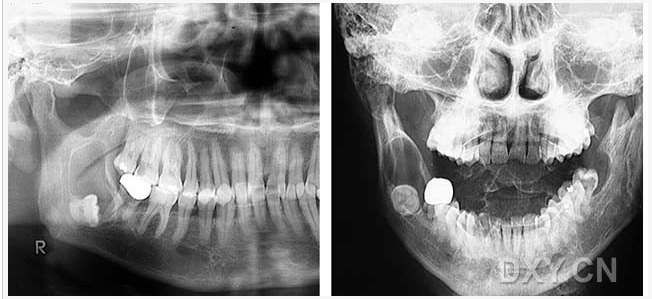

成釉細胞瘤

涎石病